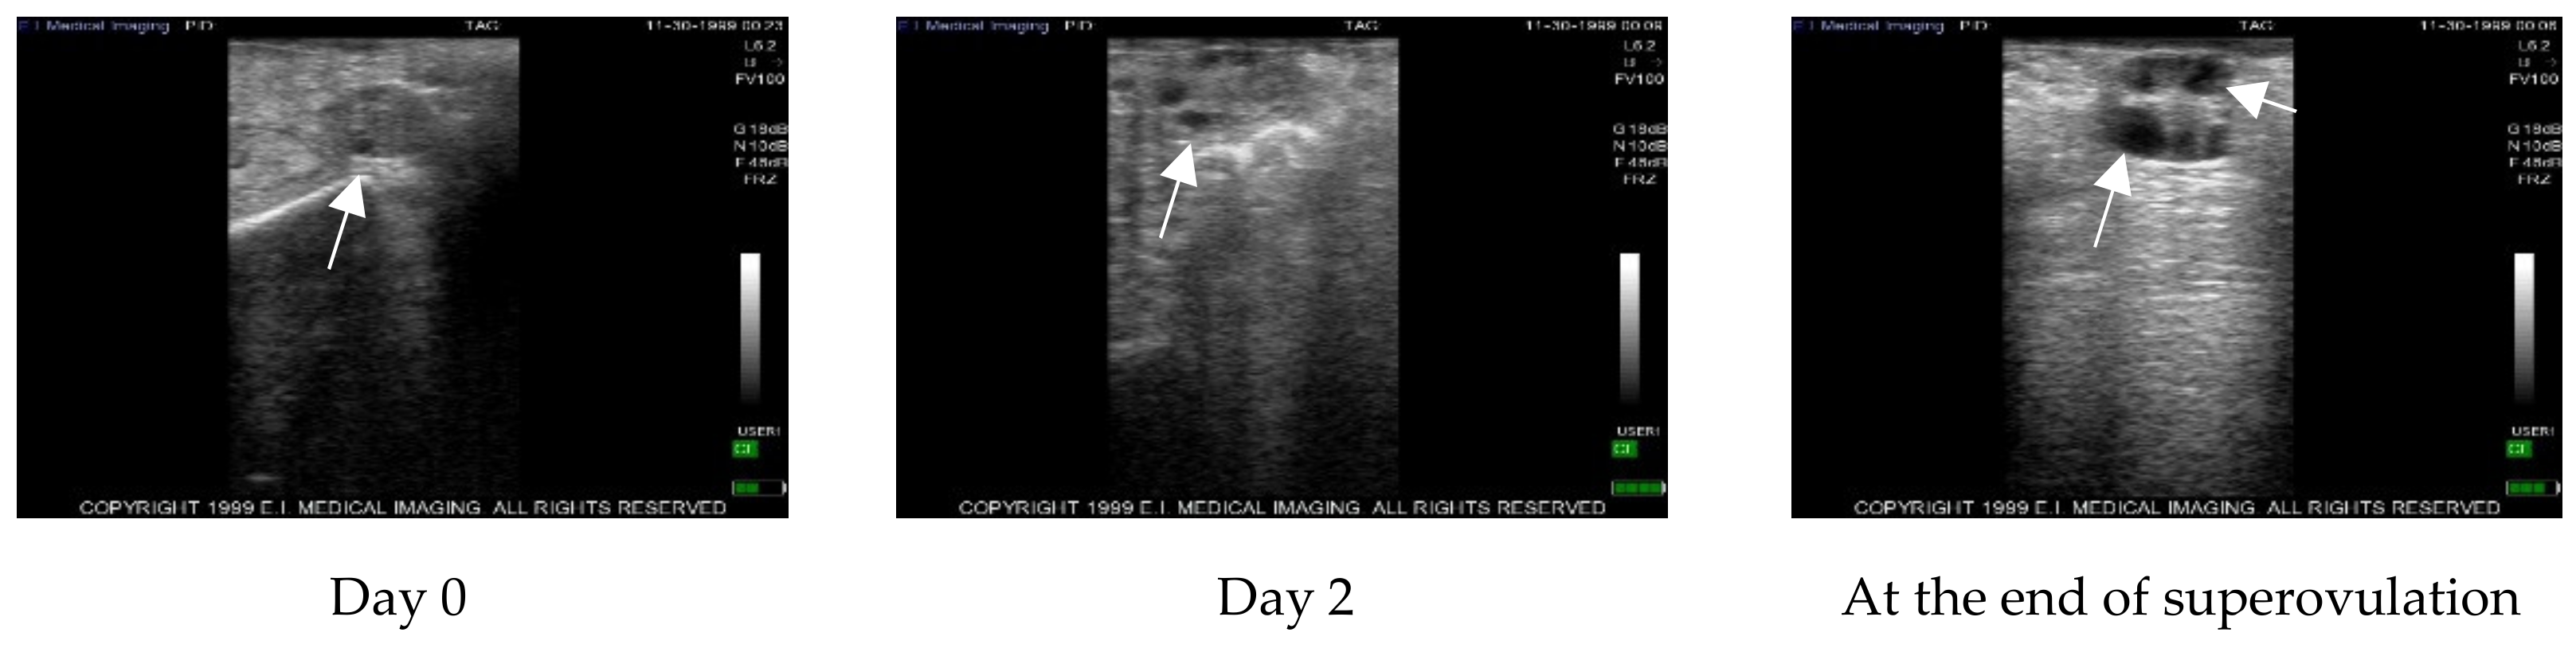

The follicular waves were monitored by ultrasound before and after PRP administration and during superovulation in control ovaries (Figure 1) and in treated ovaries (Figure 2) at the same time point.

The number of follicles before PRP treatment, two days post-treatment with PRP and after superovulation, was detected by ultrasound examination. Data are summarized in Table 2.

No statistically significant differences (p = 0.28) were detected between treated and control ovaries during the pre-treatment step or two days post-treatment with PRP. After the superovulation protocol, a statistical significant difference (p = 0.023) was detected between treated and control ovaries.

Inside the treated ovaries, a statistically significant difference was detected between pre-treatment with PRP and after superovulation (p = 0.0018).

Figure 2. Example of echographic images representing the change in follicle number during the different steps of the study in treated ovaries. Arrows indicate follicles. PRP: platelet rich plasma.